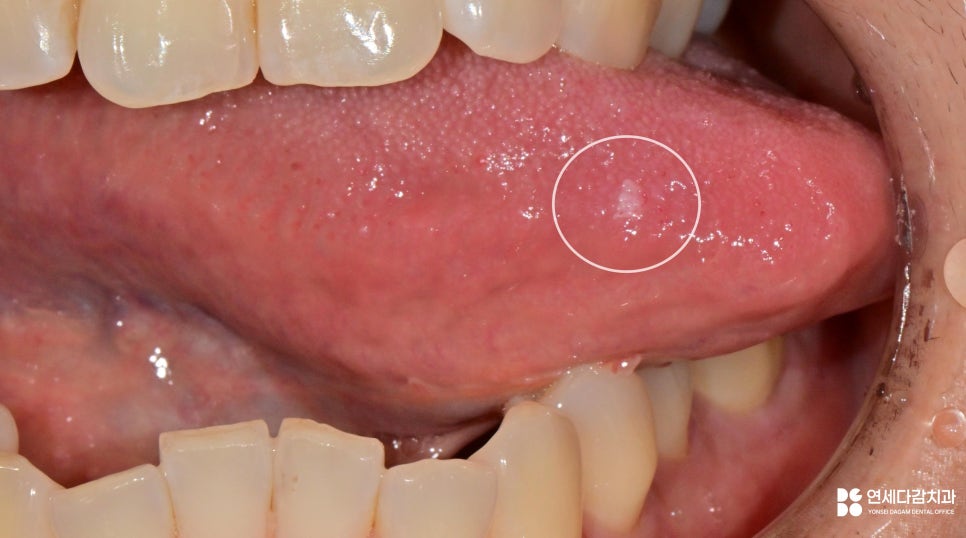

구강 유두종은 점막에 발생하는

돌출된 병변입니다.

표면이 하앟거나 분홍빛을 띠며

작은 돌기들이 모여 있는 형태가 많죠.

특히 혀에 생긴 경우에는

대화, 식사 시에도 자극을 받기 쉬워

불편감을 느끼는 분들이 많습니다.

육안으로 볼 때 일반적인 구강 유두종이여도,

다른 종류의 병변일 수 있다는 것입니다.

외형은 유사하게 보이더라도,

악성으로 이어질 수 있다는 의미이죠.

즉, 형태가 전형적으로 보인다고 해서

확진할 수 있다는 것이 아니며,

이는 정확한 진단을 위해

조직검사(생검)의 필요성을 말합니다.